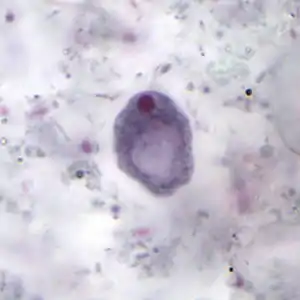

Trophozoite

The trophozoites are 9–14 micrometres in diameter. Trophozoites are one of the two forms of I. buetschlii. This form has a pseudopodia for locomotion. The pseudopodia is short and blunt. It moves in a slow manner. The trophozoite has a single nucleus, prominent for nuclear endosome and many cytoplasmic vacuoles. The ectoplasm and the granular endoplasm are often hard to distinguish. The nucleus is fairly large and vesicular, containing a large endosome, surrounding by light staining granules about midway between it and the nuclear membrane. Achromatic strands stretch between the endosome and nuclear membrane without any peripheral granules. Food vacuoles are commonly filled with bacteria and yeast. Trophozoites are often identified by a stool smear, found in loose stools.[3][4]